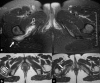

Introduction: Quadratus femoris tear is an uncommon injury, which is only rarely reported in the literature. In the majority of cases the correct diagnosis is delayed due to non-specific symptoms and signs. A magnetic resonance imaging scan is crucial in the differential diagnosis since injuries to contiguous soft tissues may present with similar symptoms. Presentation with sciatica is not reported in the few cases existing in the English literature and the reported treatment has always been conservative.

Case presentation: We report here on a case of quadratus femoris tear in a 22-year-old Greek woman who presented with persistent sciatica. She was unresponsive to conservative measures and so was treated with surgical decompression.